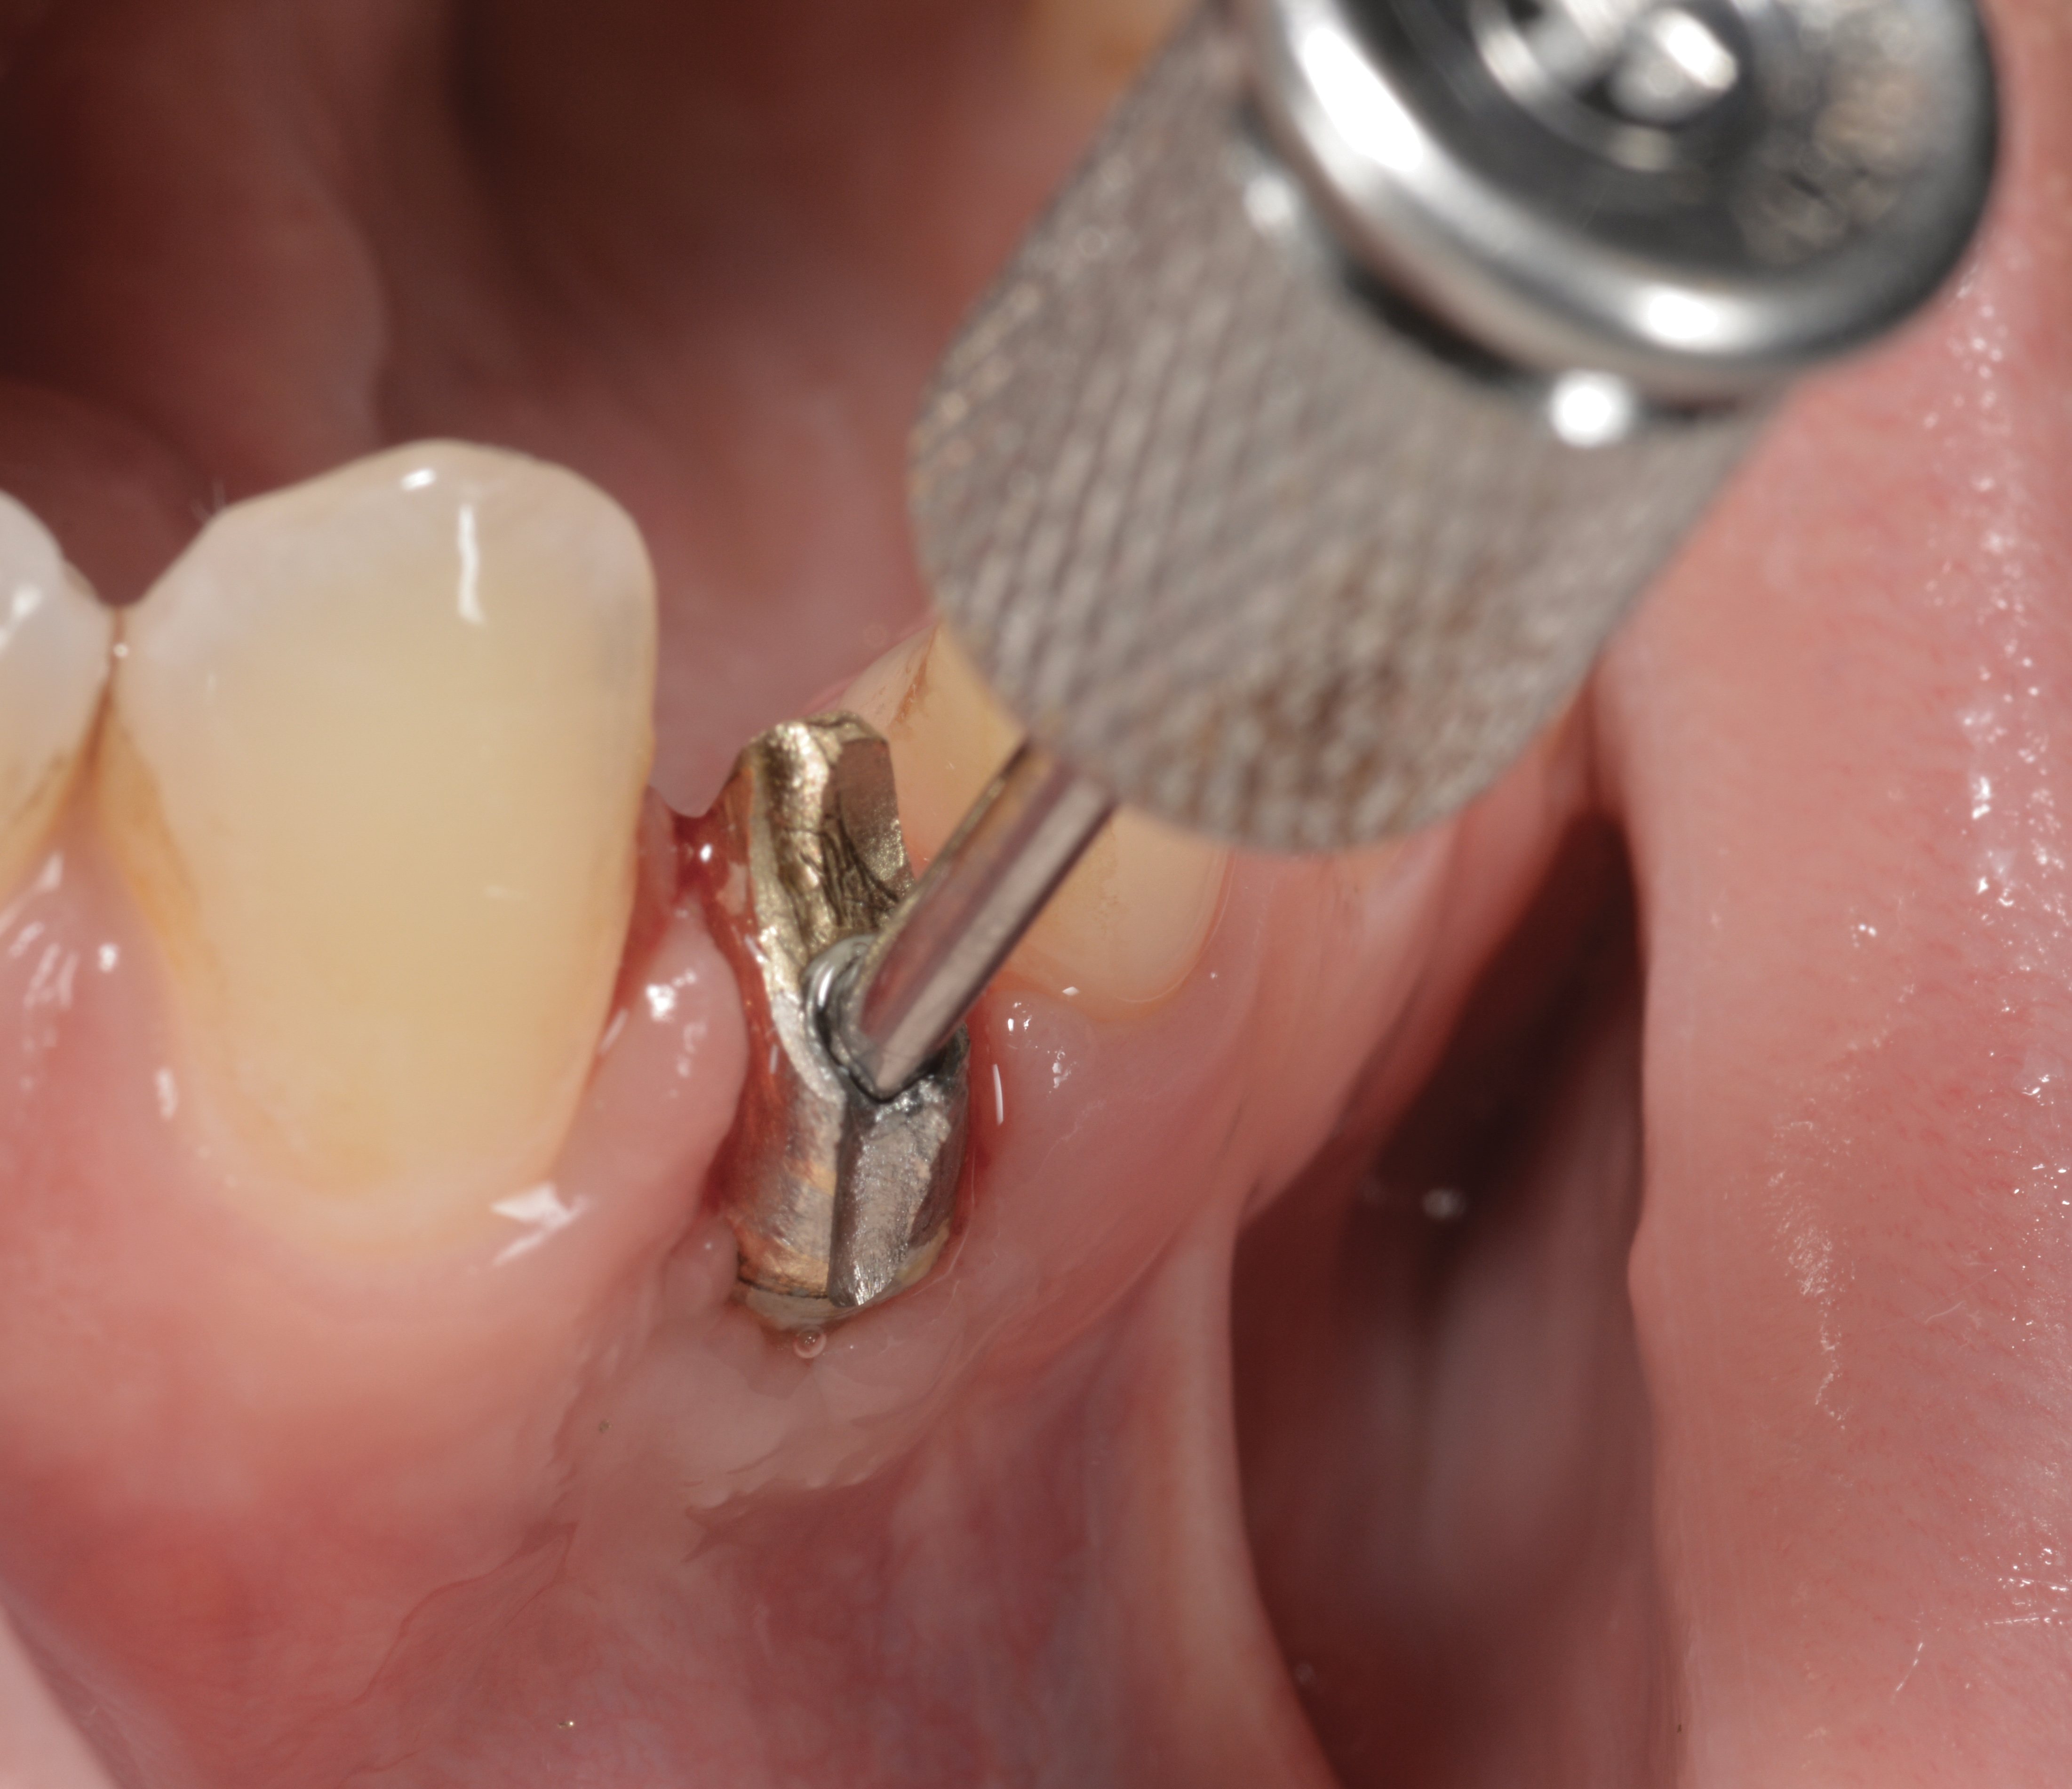

Fig 38. A reverse-torque screw was placed into the implant.

Figure 38

Fig 39. A counter-torque device was placed over the reverse-torque screw.

Figure 39

Fig 40. The implant was easily unscrewed within minutes in a minimally invasive manner with less trauma to the surgical site.

Fig 37. The reverse-torque driver can put up to 450 Ncm of force to disrupt osseointegration.

Figure 37